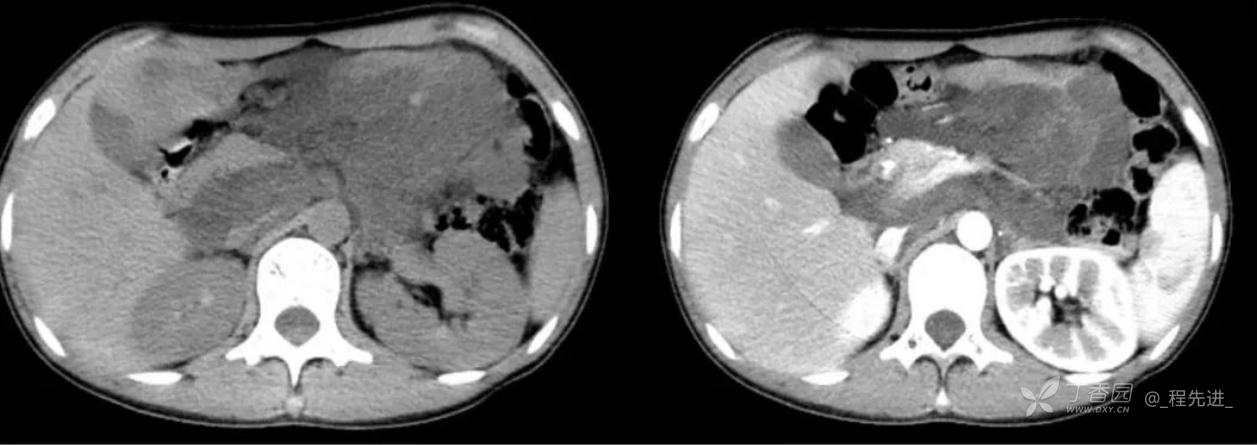

主诉:腹痛、发热一天

现病史:一天前无明显诱因出现腹痛并发热不适,伴恶心、干呕,诊所肌注药物(具体用药不详),无缓解,无明显尿频、尿痛。

体格检查:腹肌稍紧张,右上腹部轻压痛,右肾区叩痛